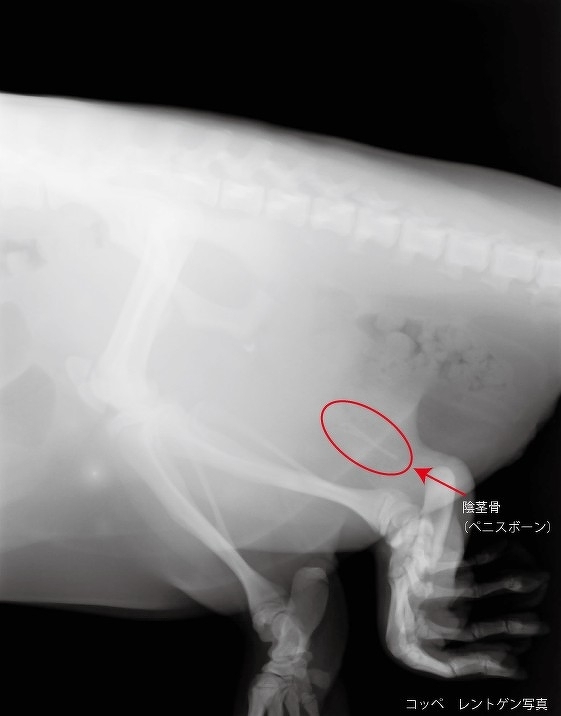

アメリカビーバー「コッペ」の性別について 2026年03月29日(日) 動物ニュース 当園で飼育しているアメリカビーバー「コッペ」の性別についてお知らせいたします。 本日麻酔下にて雌雄判別を行ったところ、レントゲン撮影で陰茎骨(ペニスボーン)が確認されたため、オスと判明しました。 ※アメリカビーバーの雌雄は外観での判断が難しく、レントゲン撮影でオスの特徴である陰茎骨の有無を確認します。